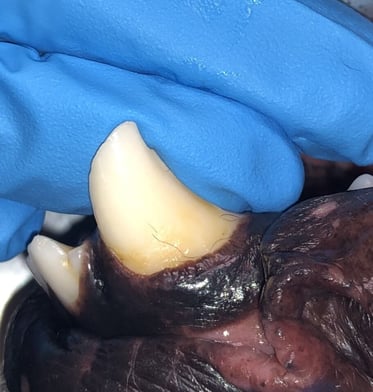

Below: Images of 304 before RCT and restoration

%20(2).jpg?width=423&height=393&name=complicated%20crown%20fracture%20(ccf)%20(2).jpg)

%20Case%202%20-%20July%202024/complicated%20crown%20fracture%20(ccf).jpg?width=373&height=280&name=complicated%20crown%20fracture%20(ccf).jpg)